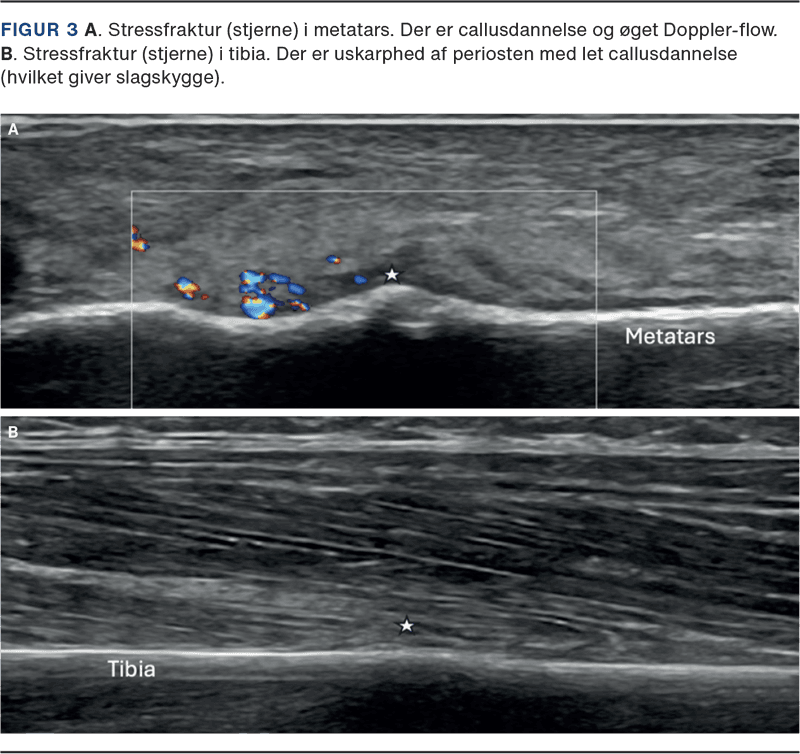

Utralydskanning

Point-of-care (klinisk) UL-skanning anvendes i stigende omfang til diagnostik af SF. Metoden er lettilgængelig, billig, effektiv og uden stråling, men er meget operatørafhængig. UL-skanning er specielt velegnet til de lange rørknogler (f.eks. tibia og metatarser), hvor sensitiviteten er højere end ved røntgenundersøgelse [15, 18]. Ved UL-skanning kan der ses selv minimale konturspring, periostale blødninger, callusdannelse og øget Doppler-flow (se Figur 3), og forandringerne kan relateres med stor sikkerhed til de kliniske symptomer [21].